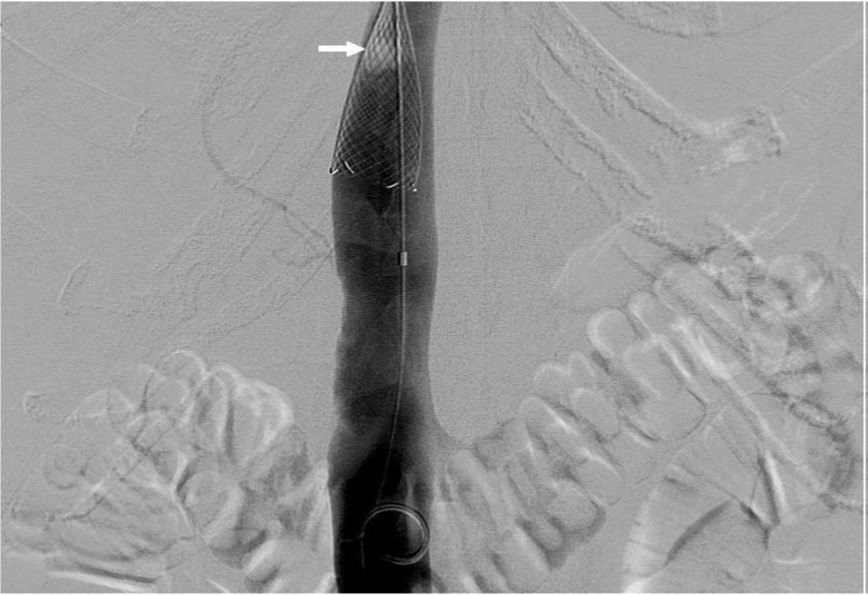

Fig. 2. B

B. Radiography obtained during partial deployment of stent as a temporary IVC filter.

Fig. 2. D

D. IVC venogram after aspiration thrombectomy shows migrated thrombus entrapped in the partially deployed stent.